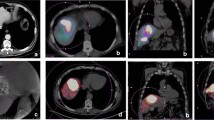

In all 47 patients, a total of 283 liver lesions with an SUV >2.5 were identified by PET. Venous contrast-enhanced CT, detected 221 (78.0%) and 15 (5.3%) of these lesions as either hypodense or hyperdense lesions, respectively. Correspondingly, 47 (16.6%) PET-positive liver lesions were not seen on venous contrast-phase CT images (Fig. 1). One hundred three of the 283 (36.4%) liver lesions detected by PET/CT were found to be located outside the field of view or the contrast-enhanced liver segments of the C-arm CT images. Of the remaining 180 lesions, 25 (8.8%) and 98 (34.6%) were identified as hyperdense lesions or hypodense lesions with a characteristic hyperattenuating rim, respectively. Although located in the contrast-enhanced liver segment, the remaining 57 (20.1%) liver lesions could not be seen on the C-arm CT images.

We have learned from our study that C-arm CT images help to detect or exclude extrahepatic accumulations of contrast material more precisely than DSA alone (Figs. 2, 3). C-arm CT was compared with Tc-MAA for the detection of extrahepatic shunting in a study by Heusner et al. In a cohort of 30 patients, the investigators reported sensitivity, specificity, positive predictive value, negative predictive value, and accuracy values of 60, 96, 75, 92, and 90%, respectively [14].

Fifty-eight year-old woman with metastases from colorectal cancer. Conventional CT (A) shows a hypodense lesion (arrowhead) in segment 6 of the liver, which contains viable tumor tissue as demonstrated by PET. B C-arm CT shows typical rim enhancement of the liver metastasis (arrowhead) and enhancement of the gall bladder wall (arrow). C RE with the catheter in this particular location may result in radionecrosis of the gall bladder and cholecystitis unless embolization of the cystic artery is performed

Fifty-three year-old woman with multifocal liver metastases originating from breast cancer. A Tumor blush in the left liver lobe is seen by the central catheter position. A further side branch to the left (arrowhead) may lead to extrahepatic or intrahepatic structures in the left upper quadrant. B The catheter was retracted, and C-arm CT was performed at this position. C C-arm CT images clearly show depicted multifocal liver metastases with rim enhancement. No contrast enhancement is detected outside the liver, e.g., in the stomach (asterisk). D Venous-phase contrast-enhanced CT at a comparable level displays bright enhancement of the stomach (asterisk)

C-arm CT is also able to provide more detailed information about tumor vascularity and from which arteries the tumors are deriving their vascular supply (Figs. 4, 5). Loui et al. reported 22 of 42 patients (52%) in whom extrahepatic enhancement or incomplete tumor perfusion was seen on C-arm CT, thus affecting the treatment plan. In 14 patients (33%), the findings were evident exclusively on C-arm CT and were not detected by DSA. This is in agreement with our findings that C-arm CT obtained additional information compared with DSA in 57.4% of patients, thus affecting treatment in 25.5% of patients prepared for RE. When comparing C-arm CT with Tc-MAA scintigraphy, C-arm CT showed eight cases of extrahepatic enhancement (19%) that were not evident on Tc-MAA imaging, according to Loui et al. [15]. Therefore, C-arm CT might have the potential to decrease the risk of therapy-induced complications, thus allowing for more sophisticated therapy planning [16].

A Sixty-nine year-old woman with cholangiocellular carcinoma presenting as a central mass in the liver. B PET/CT shows viable tumor tissue, particularly in the peripheral part of the tumor. C C-arm CT image with catheter in the right liver lobe artery shows partial enhancement of the mass. The hypervascularized portion of the tumor as presented by C-arm CT seems to correspond to the viable tumor tissue in PET/CT. Because the tumor was not reached in total from this catheter position, the catheter had to be repositioned to the left liver lobe to complete the therapy